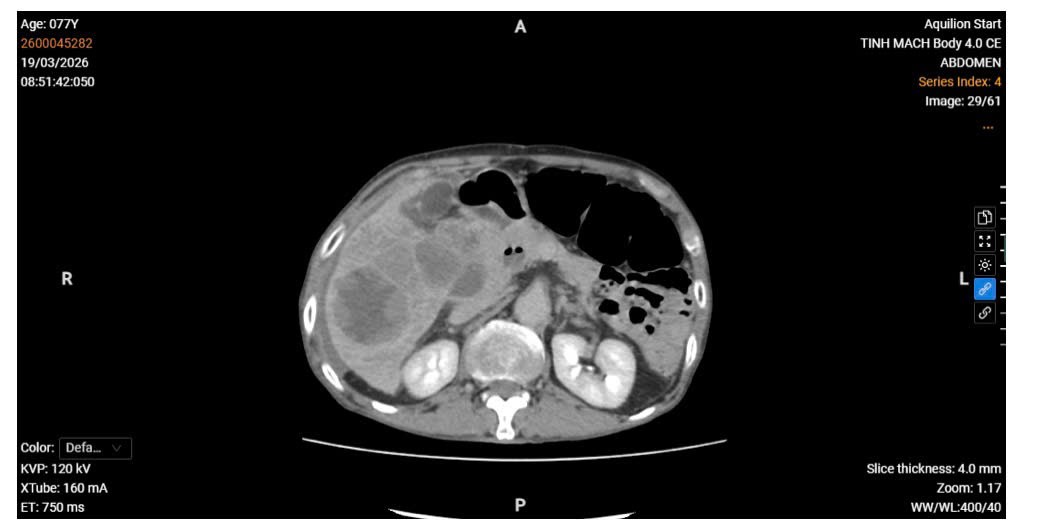

Xét nghiệm cận lâm sàng cho thấy tình trạng thiếu máu, rối loạn chức năng gan trên nền bệnh lý mạn tính. Hình ảnh chụp CT Scanner bụng có tiêm thuốc cản quang ghi nhận: gan có nhiều khối u phù hợp ung thư biểu mô tế bào gan, trong đó khối u lớn tại hạ phân thùy IV–V bị vỡ, gây chảy máu trong bao gan và một lượng dịch máu tự do trong khoang phúc mạc. Ngoài ra, phát hiện huyết khối không hoàn toàn tĩnh mạch chủ dưới và tĩnh mạch gan phải, giãn nhẹ đường mật trong gan vùng hạ phân thùy V, VI, cùng với giảm tưới máu nhu mô gan tại các phân thùy VI, VII.